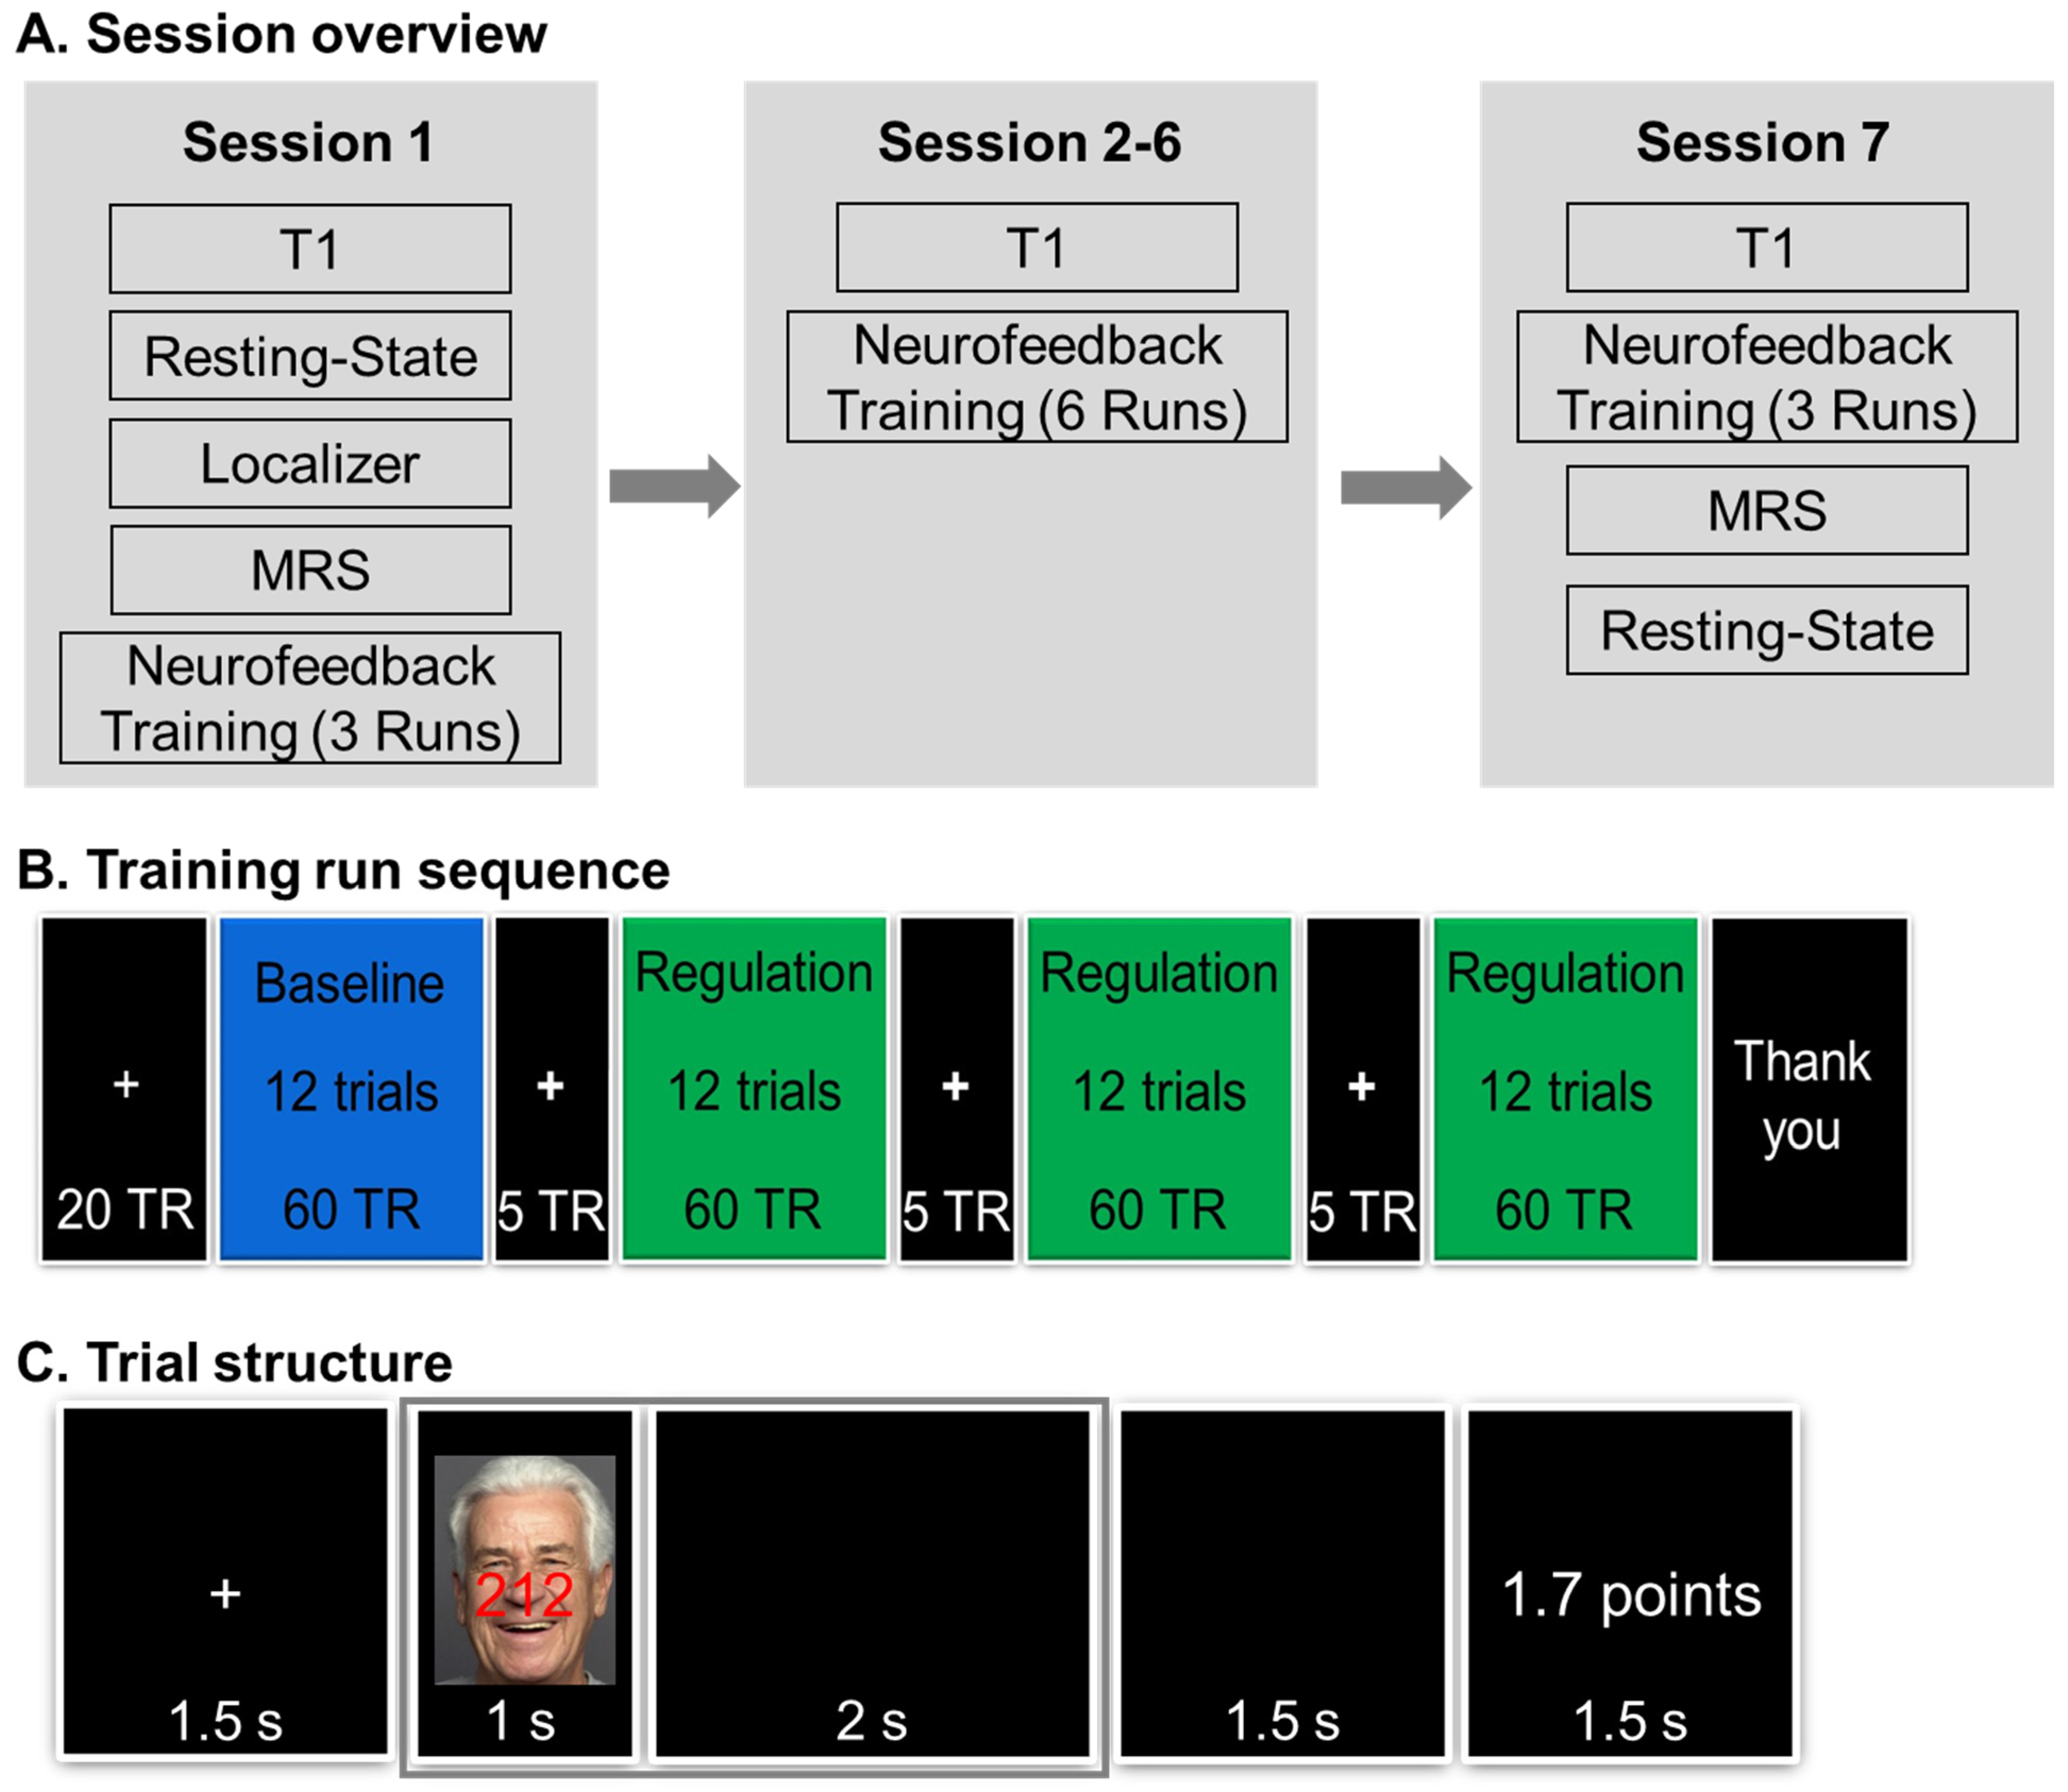

2.2. Procedure

2.2.1. Pre-Training Session

2.2.2. Neurofeedback Training Sessions

2.4. Neurofeedback Training Task

2.5. Online Data Analysis and Neurofeedback/Reward Points Calculation